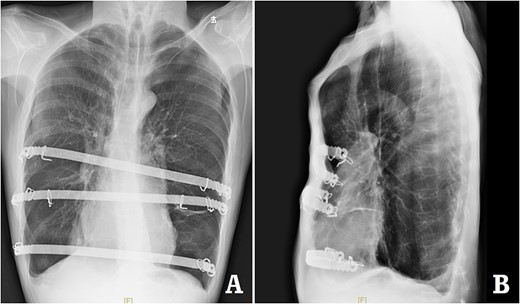

The patient was a 29-year-old male. He was found to have protrusive deformity on the anterior chest wall since childhood. The deformity was not serious in early years, but worsened after adolescence, with the lower part of the sternum protruding at an acute angle. At the age of 25, he developed right spontaneous pneumothorax and received surgical treatment at local hospital, but his thoracic deformity was not treated. As the deformity continued to worsen, which seriously affected the appearance of the chest wall, the patient was admitted to our hospital for surgery. Preoperative physical examination showed that the anterior chest wall was protrusive seriously, with a sharp tip protruding forward. The rib arches on both sides were slightly depressed (Fig. 1). Imaging examination showed that the anterior chest wall was protrusive, and the lower end of the sternum was at the forefront of the protrusion. His heart moved to the right, and the rib arches were slightly depressed (Figs 2–4). The operation was performed under general anesthesia. Two longitudinal incisions were made on both sides of the chest wall respectively. The incisions were located between the front axillary line and the median axillary line, with the length of ~5 cm. The chest wall muscles were dissected to expose the ribs in the incisions. Two tunnels were made on the highest plane of the protrusion, with interval of 3 cm. The tunnels were located in the deep layer of the chest wall muscles and bone structures. Two steel bars were inserted into the tunnels to flatten the front protrusion with their median parts, and then, both ends of the steel bars were fixed on the ribs at the lateral chest wall. The above operation was the main content of Wenlin procedure [1, 2, 5]. After this procedure was completed, the lower part of the chest wall showed obvious depression, especially in the middle of the rib arches. Then, Wung procedure was performed [6]. A third tunnel was made at the plane passing the midpoint of the rib arch, which passes through the bilateral thoracic cavity. The third steel bar was inserted into the tunnel. After the steel bar was rotated and fixed to the ribs, the depression was supported totally. The incisions were closed, and the operation was completed. The deformity of anterior chest wall disappeared completely after the operation (Fig. 5). The operation time was 75 min. The intraoperative bleeding volume was 40 ml. Postoperative X-ray examination showed that the bars position was normal (Fig. 6). He was discharged 7 days after operation. Follow up for 1 year showed satisfactory recovery. The steel bars were taken out 1 year after the operation, and the appearance of the thorax was normal and there was no recurrence (Fig. 7).

X-ray examination after operation. (A) Posteroanterior radiograph; and (B) lateral radiograph.